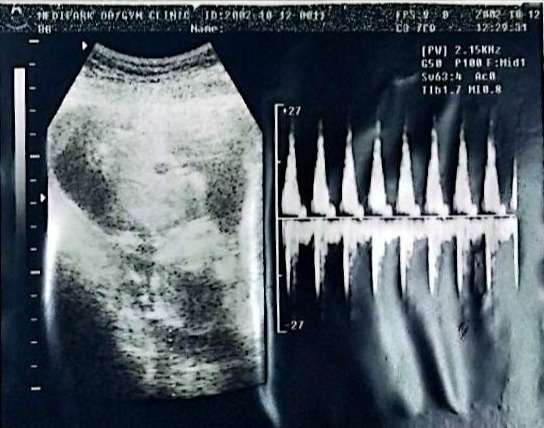

엄마는 어제(10.7) 처음으로 너의 움직임을 느꼈단다. 믿어지지 않는 기분이었어. 무언가 손에 살짝 왔다 간 기분... 아빠도 여러 차례 느껴보려고 했지만 느끼지 못해서 너무 아쉬워했단다. 빨리 아빠에게도 알려주렴. 이번 주에 너의 모습을 보러 간단다. 건강하게 자란 모습을 빨리 만나보고 싶구나

이제 우리 00 이가 아주 많이 커서 초음파로 한눈에 보이지 않는다. 정말 무럭무럭 자라는 네가 고맙다.

KakaoTalk_20250912_093314102.jpg 2002.10.12